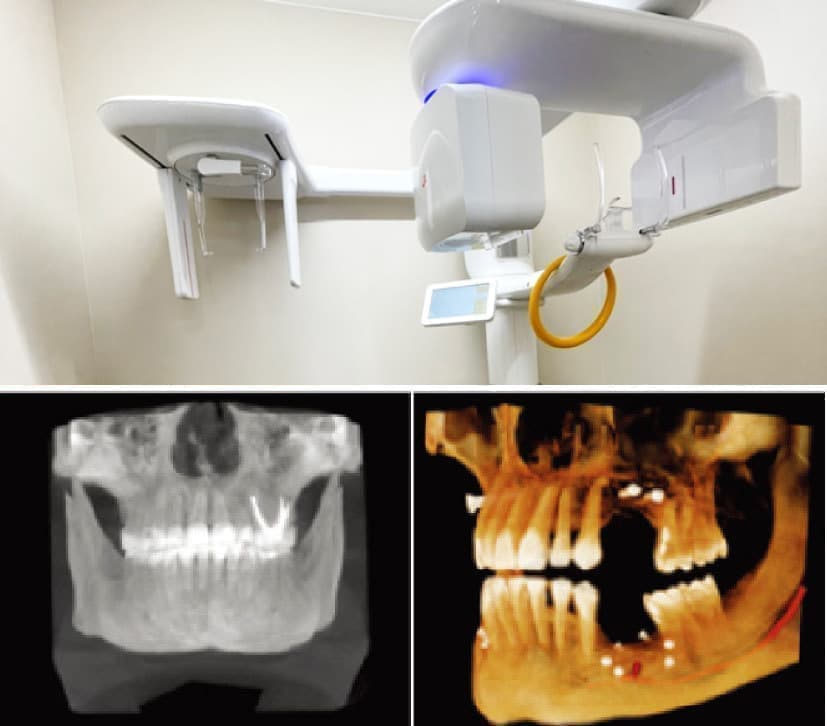

3DCT(三次元撮影機)

3 次元CT では従来の2 次元レントゲン撮影では見えなかった立体的な位置関係や骨の構造が確認でき診断の精度が飛躍的に向上します。原因のわからない痛みの診断が明確になったり、すでに病巣がある場合はその範囲の確認もできたりします。

また、今日の精密治療ではCTの撮影が必須とされており、高い精度で適切な診断や治療方針が決定できます。